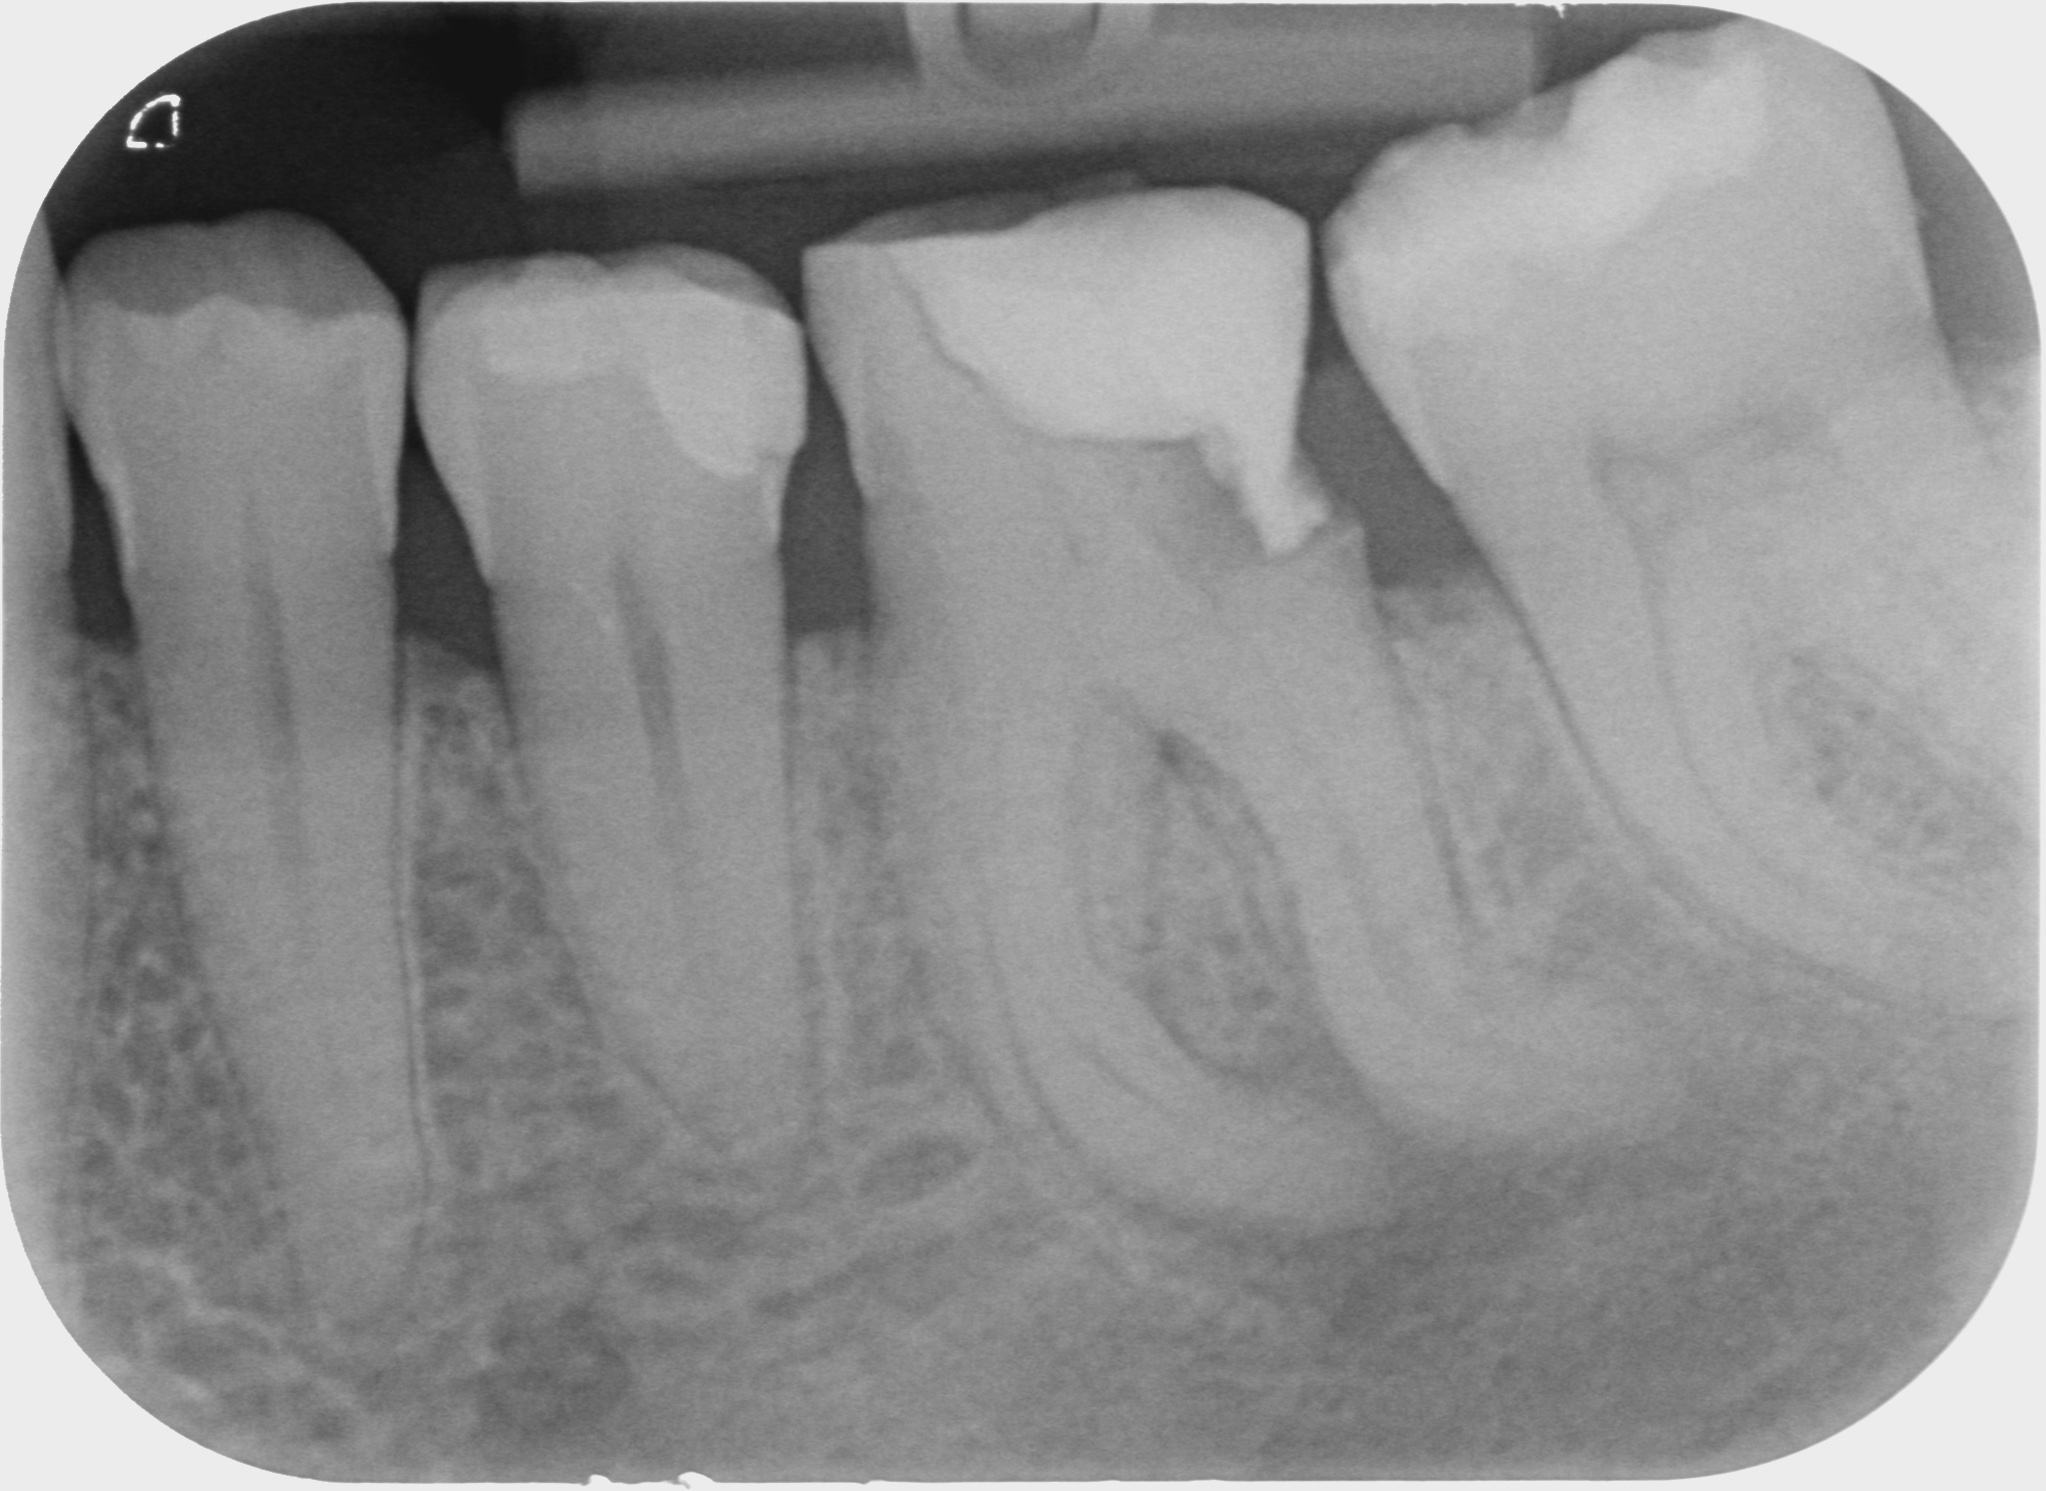

Fallbeispiele

Zum Vergrössern klicken